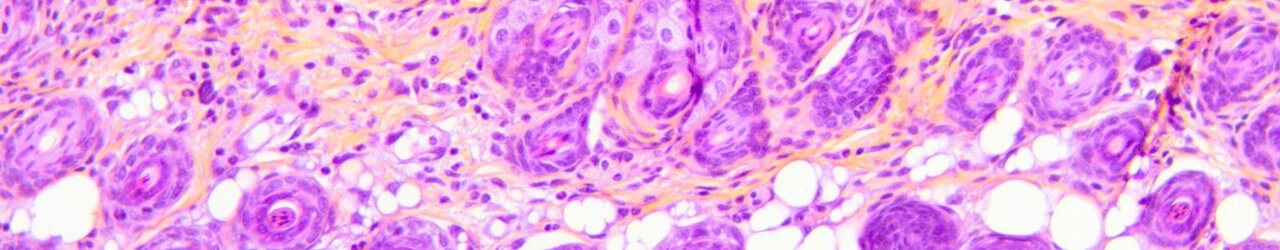

Hyperkeratosis

Repeated topical applications of TPA in mice induce skin dryness, stratum corneum thickening, and desquamation, modeling hyperkeratosis commonly observed in warts.

This model integrates in situ measurements (TEWL, dermoscopy and scoring) and histological/immunohistochemical analyses. It offers high predictive value for clinical success and constitutes a robust tool to evaluate therapeutic efficacy.